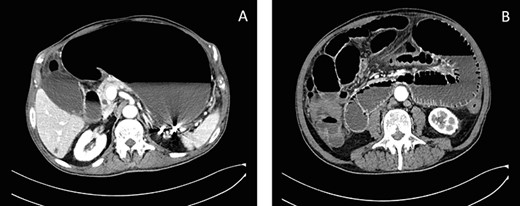

A supra-umbilical Hasson’s port was inserted and exploratory laparoscopy showed turbid effusion in Morrison’s pouch, spleno-renal pouch and pouch of Douglas. Two more trocars of 10 mm were inserted. Running the small bowel, a loop appeared densely adherent to the bladder and releasing the bowel from adhesions a bladder hole was found out (Fig. 3). The rupture of a bladder diverticulum was tamponade by an ileal loop and was critically inflaming the peritoneal cavity. An accurate laparoscopic adhesiolysis was performed. The ileal loops appeared vital and no bowel resection was necessary. The bladder hole was sutured with a knotless barbed suture. Dilute methylene blue was injected into the urinary catheter to check the watertight closure. No blue spreading was seen and a drain was inserted into pelvis. The surgery was performed by a skilled general surgeon and the consultant urologist wasn’t necessary.

Intraoperative findings of the bladder diverticulum, before (A) and after (B) suture.